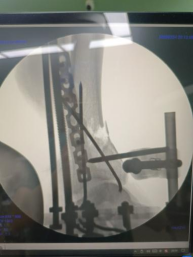

術(shù)中透視脛腓骨遠(yuǎn)端,予以克氏針臨時固定。

腓骨予以重建內(nèi)固定板固定。

三臂十一軸機(jī)器人輔助器牽引,安裝外固定架,透視檢查骨折端對位對線良好。